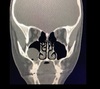

1

Not at all